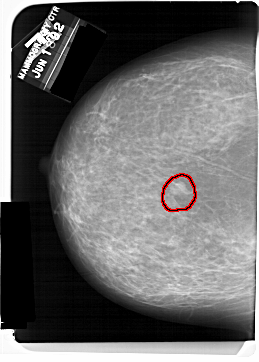

FILE: A_1560_1.LEFT_CC.OVERLAY

TOTAL_ABNORMALITIES 1

ABNORMALITY 1

LESION_TYPE MASS SHAPE LOBULATED MARGINS OBSCURED

ASSESSMENT 4

SUBTLETY 4

PATHOLOGY BENIGN

TOTAL_OUTLINES 1

BOUNDARY